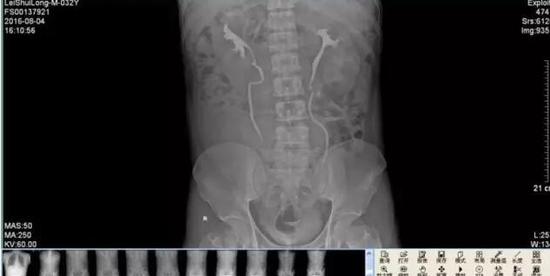

几天后,雷先生来到医院做进一步检查,令雷先生和医生们吃惊的是,腹腔巨大囊肿其实是右侧重复肾输尿管肿大,最大直径竟有13厘米,而正常人的输尿管只有0.8厘米粗,最终,雷先生被确诊患有罕见的巨输尿管症,医院根据雷先生的情况对其右侧重复肾上半肾、重复输尿管进行了切除,术后恢复良好。

医院泌尿外科主任庄海南介绍,这种病属先天性双侧双肾、双输尿管重复畸形,十分罕见,大约10万人里才会遇到一个。据了解,当人胚胎在第六周时,中肾管末端通入泄殖腔处,向背侧突出一小的盲管,称为输尿管芽。输尿管芽迅速成长发育成肾盂,分支形成肾盏,再分支形成小盏、集合管。如分支过早,则形成重复的输尿管畸形,且重复输尿管常伴发重复内脏。